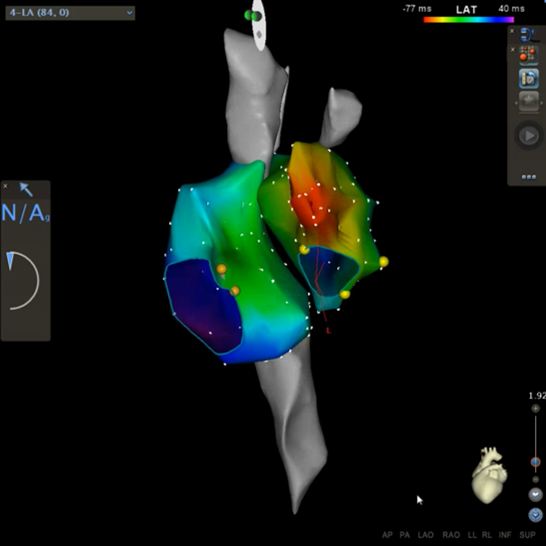

So können mit sogenannten 3 dimensionalen Ortungssystemen (Mappingsystemen – CARTO® 3 System, Enside® System) die Herzrhythmusstörungen erfasst werden und die elektrische Erregung des Herzens in einem dreidimensionalen Computermodell dargestellt werden (vergleichbar mit einer elektrischen Landkarte der Herzrhythmusstörung mit frühen und späten elektrischen Arealen). Darüber hinaus kann der elektrische Impuls des Herzens in seinem Ablauf dargestellt werden. Dieses erleichtert den Mechanismus der Herzrhythmusstörung zu erkennen und den Ursprungsort der Herzrhythmusstörung punktgenau zu erfassen.

Bild 1a und 1b: Dreidimensionale, virtuelle Darstellung der Herzvorhöfe (farbig) und der großen Venen (grau) mit CARTO 3 Uniview®.

Dargestellt sind ein rechtsseitlicher (Bild 1a) und linksseitlicher (Bild 1b) Blick auf das Herz mit Röntgenbild im Hintergrund (Bild 1a). Die Vorhofherzrhythmusstörung bei diesem Patienten hatte seinen Ursprung im linken Herzvorhof dargestellt durch die rot-orange Farbe, welche die früheste elektrische Erregung kodiert während die violette Farbe die späteste elektrische Erregung während des Herzzyklus darstellt. Die roten Punkte stellen den Ort dar, an dem die Herzrhythmusstörung unter Verödung aufhörte.

Bild 2: virtuelle Darstellung des linken Herzvorhofs mit angrenzenden Lungenvenen.

Die Farben kodieren den Ablauf der elektrischen Erregung des Herzens während eines Herzschlages mit frühen (rot-orangen) und späten (violetten) Bereichen beide Bereiche grenzen aneinander (rote Trennlinie). Somit kreist diese Rhythmusstörung um die Herzklappe (Mitralklappe – Öffnung in dem Modell des Herzvorhofes).